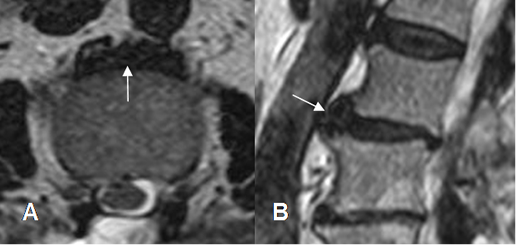

Fig 102. Hernia foraminal.

A y B: TAC axial. Obliteración de la grasa foraminal, con imágenes con densidad de tejido blando, que corresponden a hernias.

Fig 103. Hernia foraminal.

A: RM axial en T2 y B: RM axial en T1. Obliteración de la grasa foraminal, con imágenes con densidad de tejido blando, que corresponden a hernias.